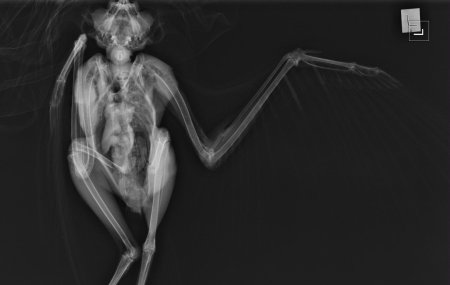

Рентгеновский эффект создает фантастические композиции в этих фотографиях девушки, чье тело становится прозрачным, демонстрируя скелет и внутренние органы. Она позирует в разных позах, ее силуэт светится загадочным свечением. Каждый кадр передает атмосферу научной фантастики и медицинского искусства. Ее кожа кажется полупрозрачной, позволяя увидеть кости и мышцы. Фотографии рассказывают о хрупкости человеческого тела и его внутренней красоте. Девушка то стоит в задумчивости, то делает грациозное движение. Эти иллюстрации вдохновляют на размышления о человеческой анатомии и уязвимости. Каждая картинка - это момент прозрения, когда внешнее уступает место внутреннему. Девушка воплощает образ современной Медузы, сочетающей красоту и загадочность.

Сквозь материю: тайны анатомии